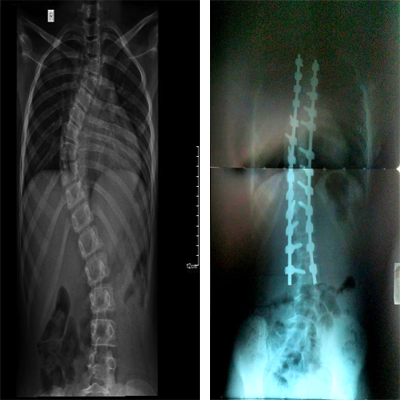

. العلاجات الجراحية لمرض الجنف (اعوجاج العمود الفقري)

ويُعد مرض الجنف (اعوجاج العمود الفقري) مشكلة شائعة لدى الأطفال والمراهقين. ولحسن الحظ، نادرًا ما يكون التدخل الجراحي ضروريًا. ومن الوسائل العلاجية للسيطرة الفعالة على هذا المرض التدعيم والعلاج الطبيعي. إذ نوفر جبيرة ومثبِّت الفقرات الصدرية والقطنية والعجزية (TLSO) وحزام ريغو تشينو والعلاج الطبيعي بتمرينات مخصصة لعلاج الجنف (اعوجاج العمود الفقري). وفي الحالات الشديدة، نلجأ إلى الخيارات الجراحية التي تعمل تصحيح اعوجاج العمود الفقري مع الحفاظ على حركة العمود الفقري.